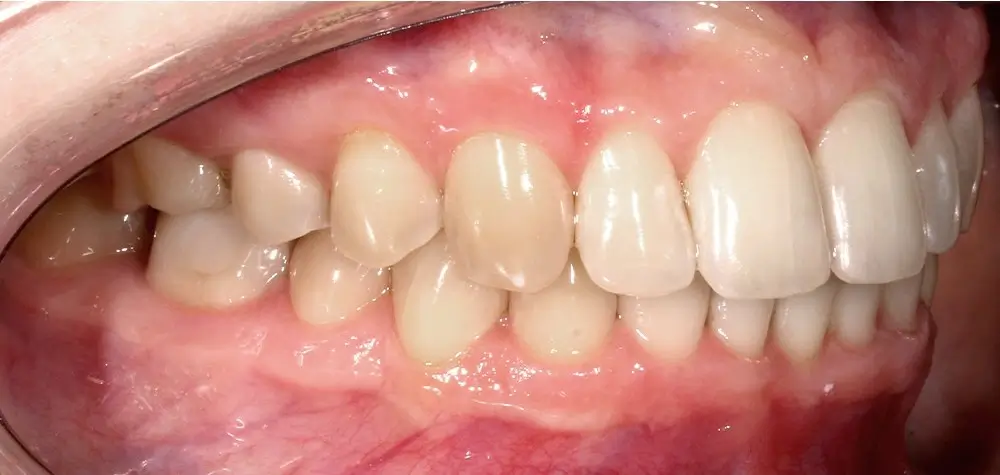

Кейс 13

Булгач (Мочалова) Галина Игоревна

Количество кап ВЧ 19

Количество кап НЧ 24

ДО

ПОСЛЕ